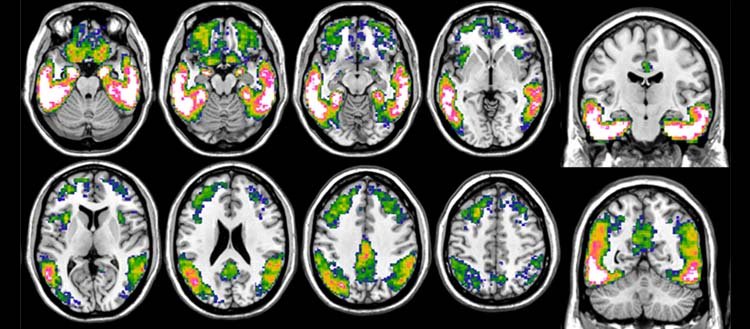

Scansione PET della tau con 18F-Flortaucipir nell'Alzheimer. Un modello prototipico di accumulo di tau, ottenuto confrontando il carico di tau nei pazienti con Alzheimer e nei controlli sani. La scala blu-bianco indica carichi tau più pronunciati, le aree rosa-bianche rappresentano quelle con il maggior accumulo. Fonte: ©UNIGE